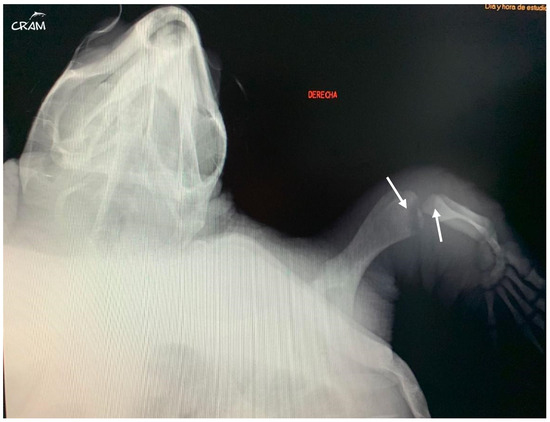

In March 2019, the same turtle, then identified as CC19/037, was accidentally captured by a trawler ship and presented moderate-to-severe gas embolism (Figure 1), based on the classification proposed by García-Párraga et al. (2014). DCS was diagnosed by radiography and response to hyperbaric chamber treatment. An injury at the level of both fifth lateral (costal) scutes of the carapace (Figure 2) was also present. The treatment for DCS was hyperbaric air at 1.6 atm pressure inside a hyperbaric chamber and 5 mg kg−1 enrofloxacin, IM q 48 h for 15 days, with debridement and curettage of the wound. The turtle was released from the beach in May 2019.

Figure 1. Dorsoventral radiograph of CC19/037 with GE of moderate-to-severe degree. Gas is evident in precava (PrC) and postcava (PsC) veins, sinus venosus (SV), gastric vessels (G), marginocostal vessels (MC), and renal portal vessels (RP).